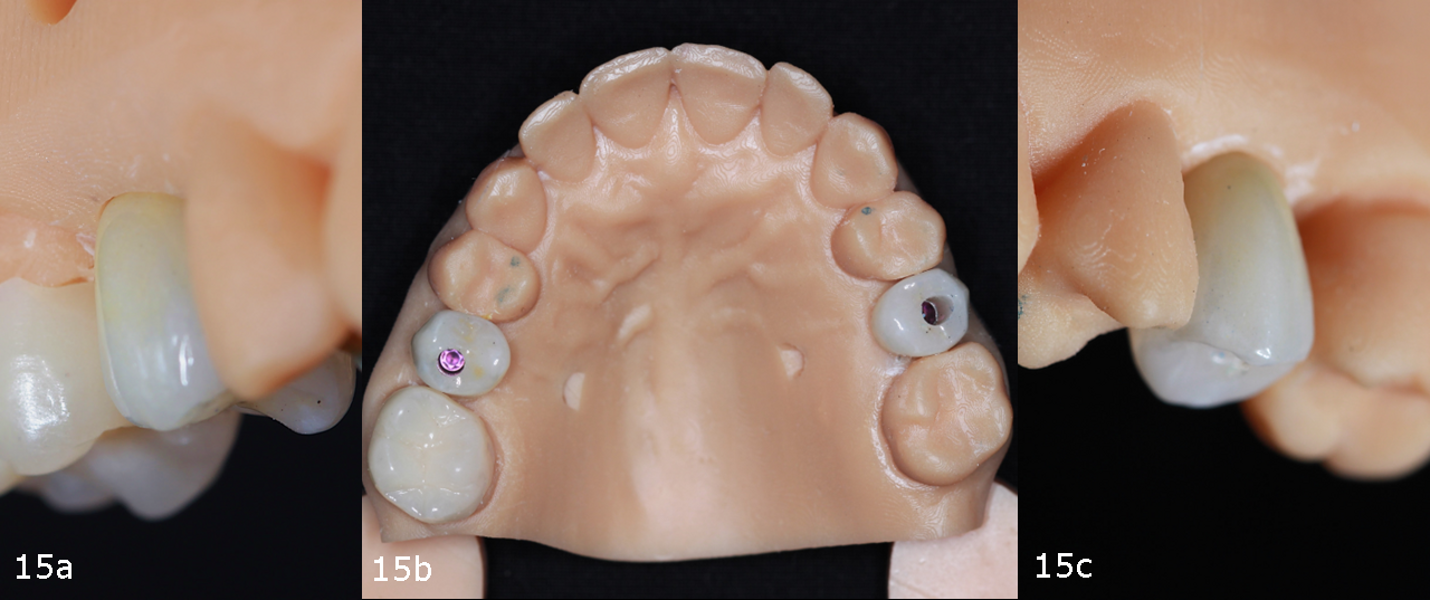

Two monolithic zirconia crowns were milled and cemented on to Straumann Variobase abutments with the same gingival height as that of the healing abutments. The crowns were tested on a 3D-printed model to evaluate occlusion and excursive movements (Figs. 15a–c). Additionally, site #16 received a temporary three-quarter onlay.